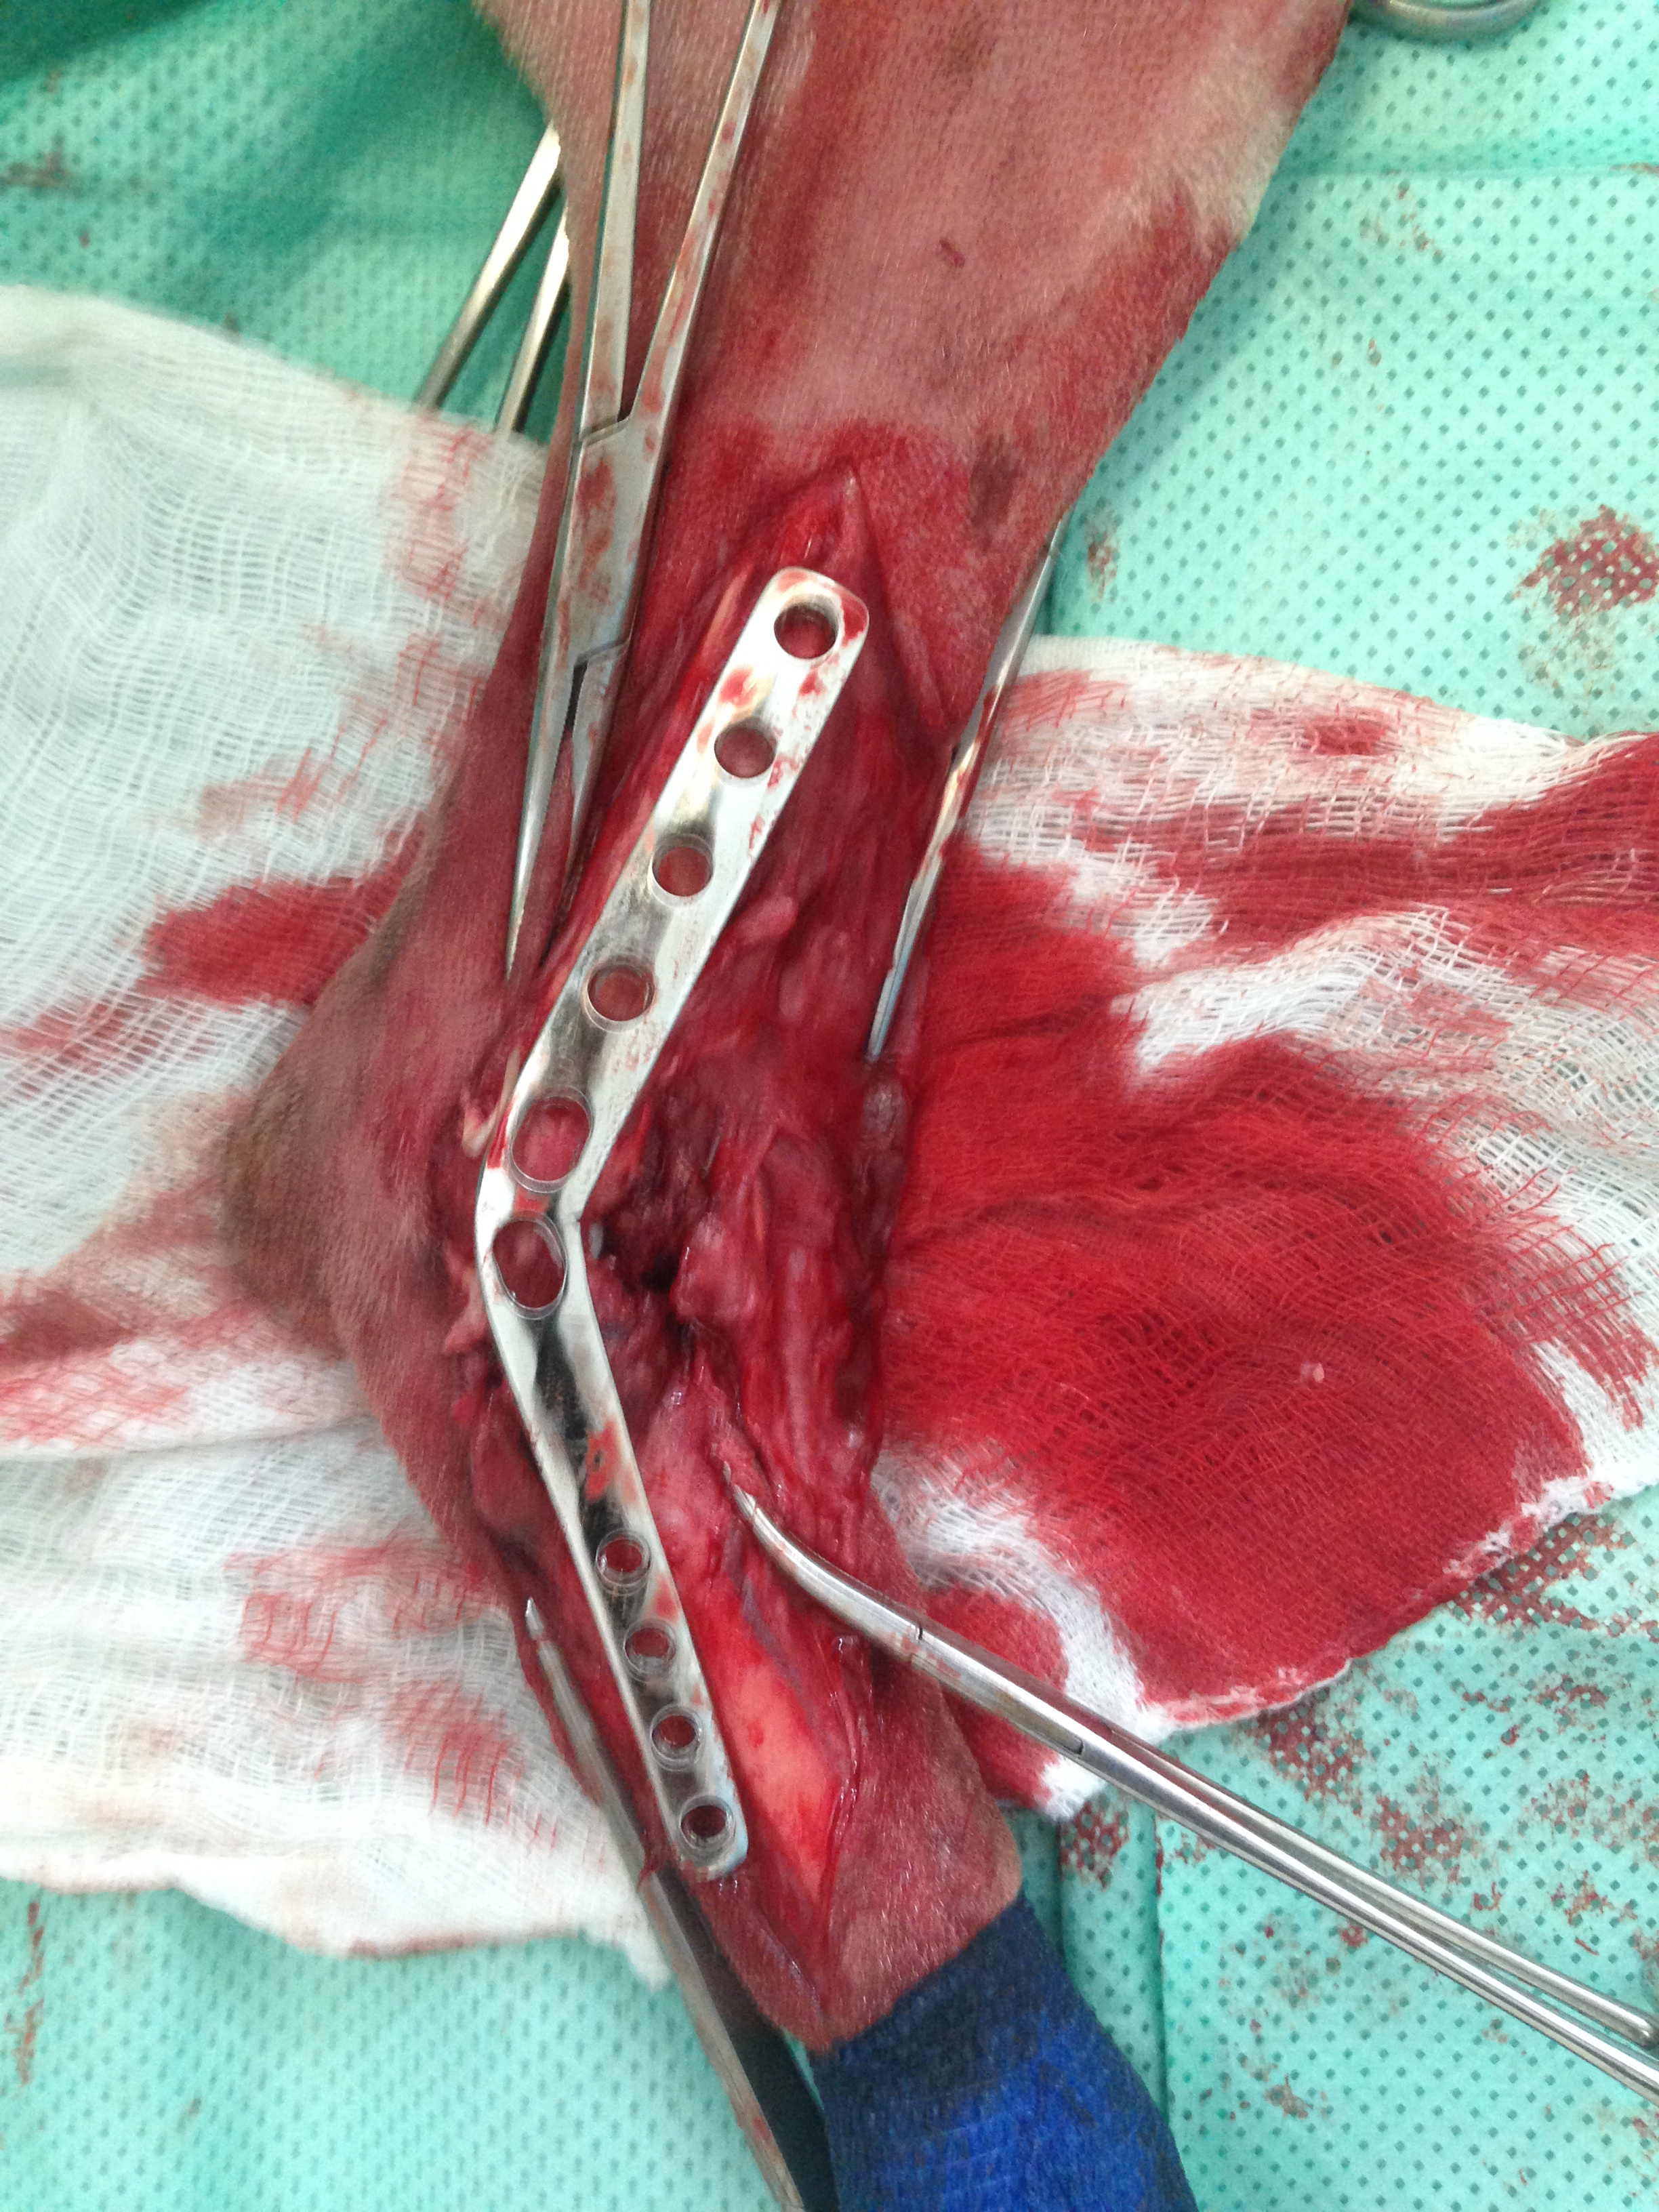

Casos Interessantes > ARTRODESE Tíbio-Tarsica por placa medial

Veja algumas Fotos